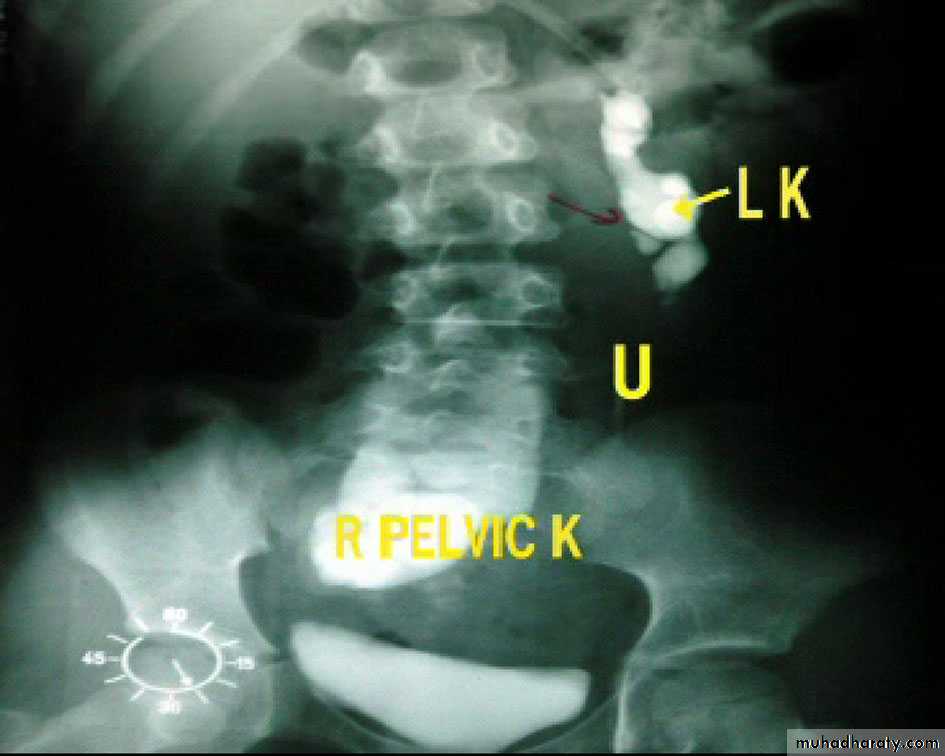

*Ectopic left kidney:-ureter is short (small arrow)

*Hydronephrosis + ectopic left kidney

*Hydronephrosis&ectopic kidney